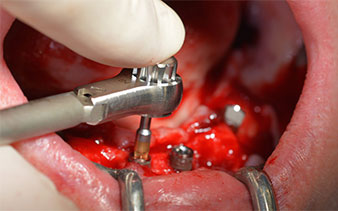

Le trou mentonnier doit d'abord être identifié comme une structure anatomique limitante, puis l'os cortical de la crête a été régularisé avec une pièce à main droite et une fraise sphérique de grande taille (Fig. 4).

C'est ici que l'Implantmed révèle ses premiers avantages. Le protocole chirurgical est prédéfini et les réglages sont enregistrés à des positions fixes. Les positions individuelles peuvent être sélectionnées en appuyant sur la position "P" de la commande au pied ou sur l'écran. La vitesse de 35,000 tr./min. à la position 1 dans ce cas apparaît aussi par de grands chiffres sur l'écran rétroéclairé (Fig 5 et 6).